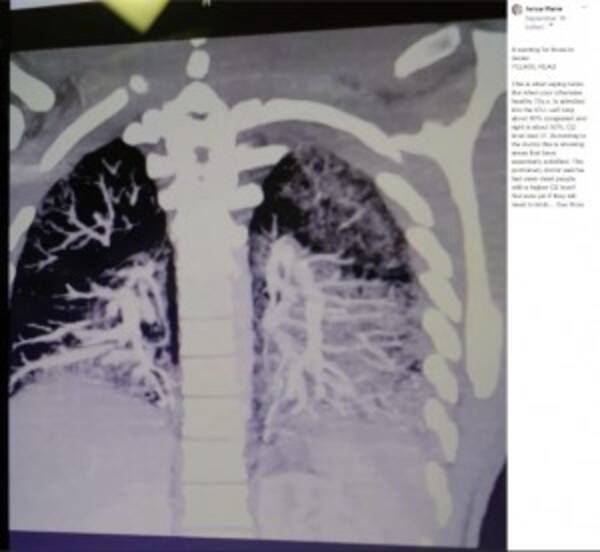

レベル2:(前期研修医)肺野,肺血管影をみて,正常と 異常の区別がつく. レベル3:粒状影,線状影,網状影,輪状影の区別がつく. レベル4:(エキスパート)単純写真からct画像が想像できる.タバコ のイラスト素材1 ページ目 (12,5件中 1件 0件を表示) このページでは、 タバコ のイラスト画像の商品を一覧でご紹介しています。 PIXTAの イラスト素材 は、高品質で低価格。 画像定額制プラン をご利用なら1点39円からご購入可能です 電子タバコのオイルが溜まった肺(画像は『Tanya Marie 19年9月16日付Facebook「A warning for those in denial PLEASE READ」』のスクリーンショット)